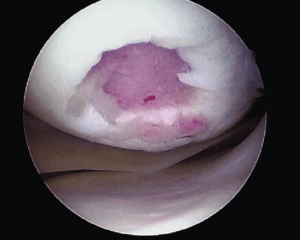

Локальное травматическое повреждение коленного сустава, вид через артроскоп.

Лечение локальных хондральных дефектов до сих пор остается сложной и противоречивой проблемой ортопедии. Многолетние усилия врачей и исследователей направлены на поиск оптимального решения, которое позволило бы восстанавливать “изношенный” гиалиновый хрящ в области максимальной нагрузки.